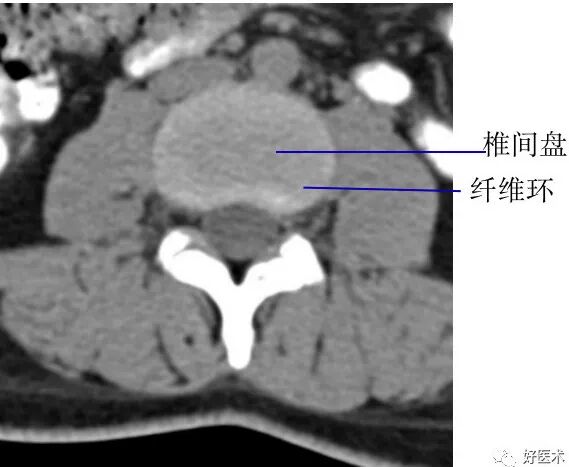

3. 经椎间盘的横断层面:

断面经过的部位:椎间盘

主要特征:椎管呈不完整的骨性环,其断开处为椎间孔下部,不同部位椎间孔下部经过的结构不同,颈段主要为脊神经根,胸腰段主要为椎间静脉。

椎间盘:呈软组织密度影,CT值为70±5HU,不能区分髓核和纤维环

髓核:T2WI上呈较高信号

纤维环:T1WI和T2WI上均显示为低信号